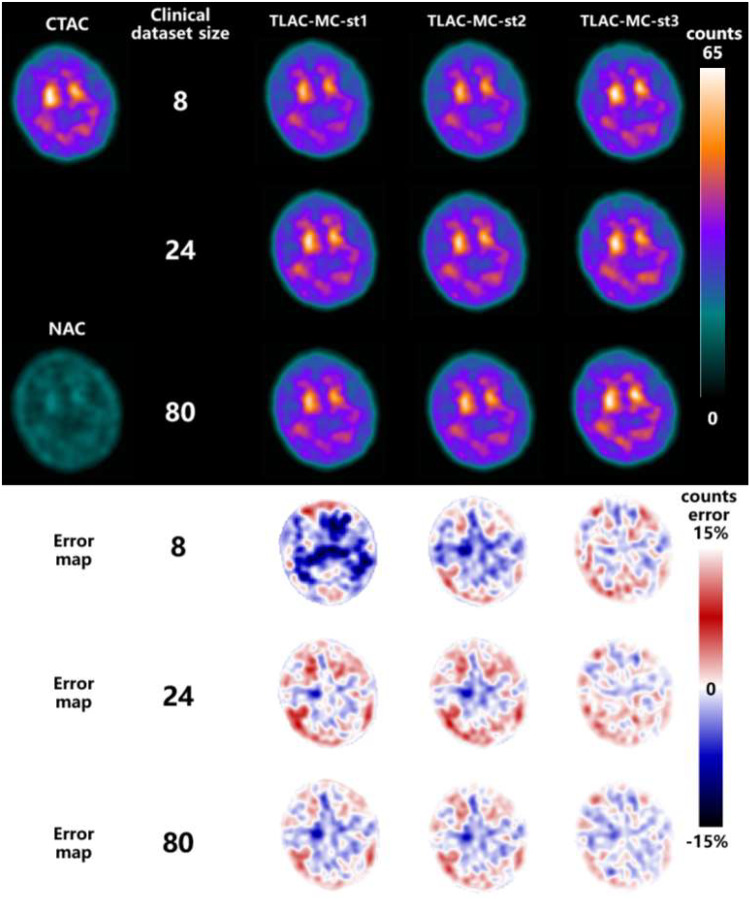

Methods: A total number of 200 digital brain phantoms with realistic 99mTc-TRODAT-1 distribution was used to generate realistic noisy SPECT projections using MC SIMIND program and an analytical projector. One hundred real clinical 99mTc-TRODAT-1 brain SPECT data were also retrospectively analyzed. All projections were reconstructed with and without CT-based attenuation correction (CTAC/NAC). A 3D conditional generative adversarial network (cGAN) was pre-trained using 200 pairs of simulated NAC and CTAC SPECT data. Subsequently, 8, 24, and 80 pairs of clinical NAC and CTAC DAT SPECT data were employed to fine-tune the pre-trained U-Net generator of cGAN (TLAC-MC). Comparisons were made against without FT (DLAC-MC), training on purely limited clinical data (DLAC-CLI), clinical data with data augmentation (DLAC-AUG), mixed MC and clinical data (DLAC-MIX), TL using analytical simulation data (TLAC-ANA), and Chang's AC (ChangAC). All datasets used for DL-based methods were split to 7/8 for training and 1/8 for validation, and a 1-/2-/5-fold cross-validation were applied to test all 100 clinical datasets, depending on the numbers of clinical data used in the training model.

Results: With 8 available clinical datasets, TLAC-MC achieved the best result in Normalized Mean Squared Error (NMSE) and Structural Similarity Index Measure (SSIM) (TLAC-MC; NMSE = 0.0143 ± 0.0082/SSIM = 0.9355 ± 0.0203), followed by DLAC-AUG, DLAC-MIX, TLAC-ANA, DLAC-CLI, DLAC-MC, ChangAC and NAC. Similar trends exist when increasing the number of clinical datasets. For TL-based AC methods, the fewer clinical datasets available for FT, the greater the improvement as compared to DLAC-CLI using the same number of clinical datasets for training. Joint histograms analysis and Bland-Altman plots of SBR results also demonstrate consistent findings.

Conclusion: TLAC is feasible for DAT SPECT with a pre-trained model generated purely based on simulation data. TLAC-MC demonstrates superior performance over other DL-based AC methods, particularly when limited clinical datasets are available. The closer the pre-training data is to the target domain, the better the performance of the TLAC model.